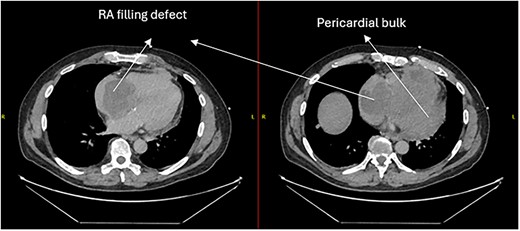

Follow-up CT scans were undertaken during chemotherapy that showed continued reduction in the size of the RA tumour, as demonstrated in Figs 4 and 5. The pericardial mass following chemotherapy is visualized in Fig. 6.

Post-operative CT scan showing further reduction of RA bulk following chemotherapy.